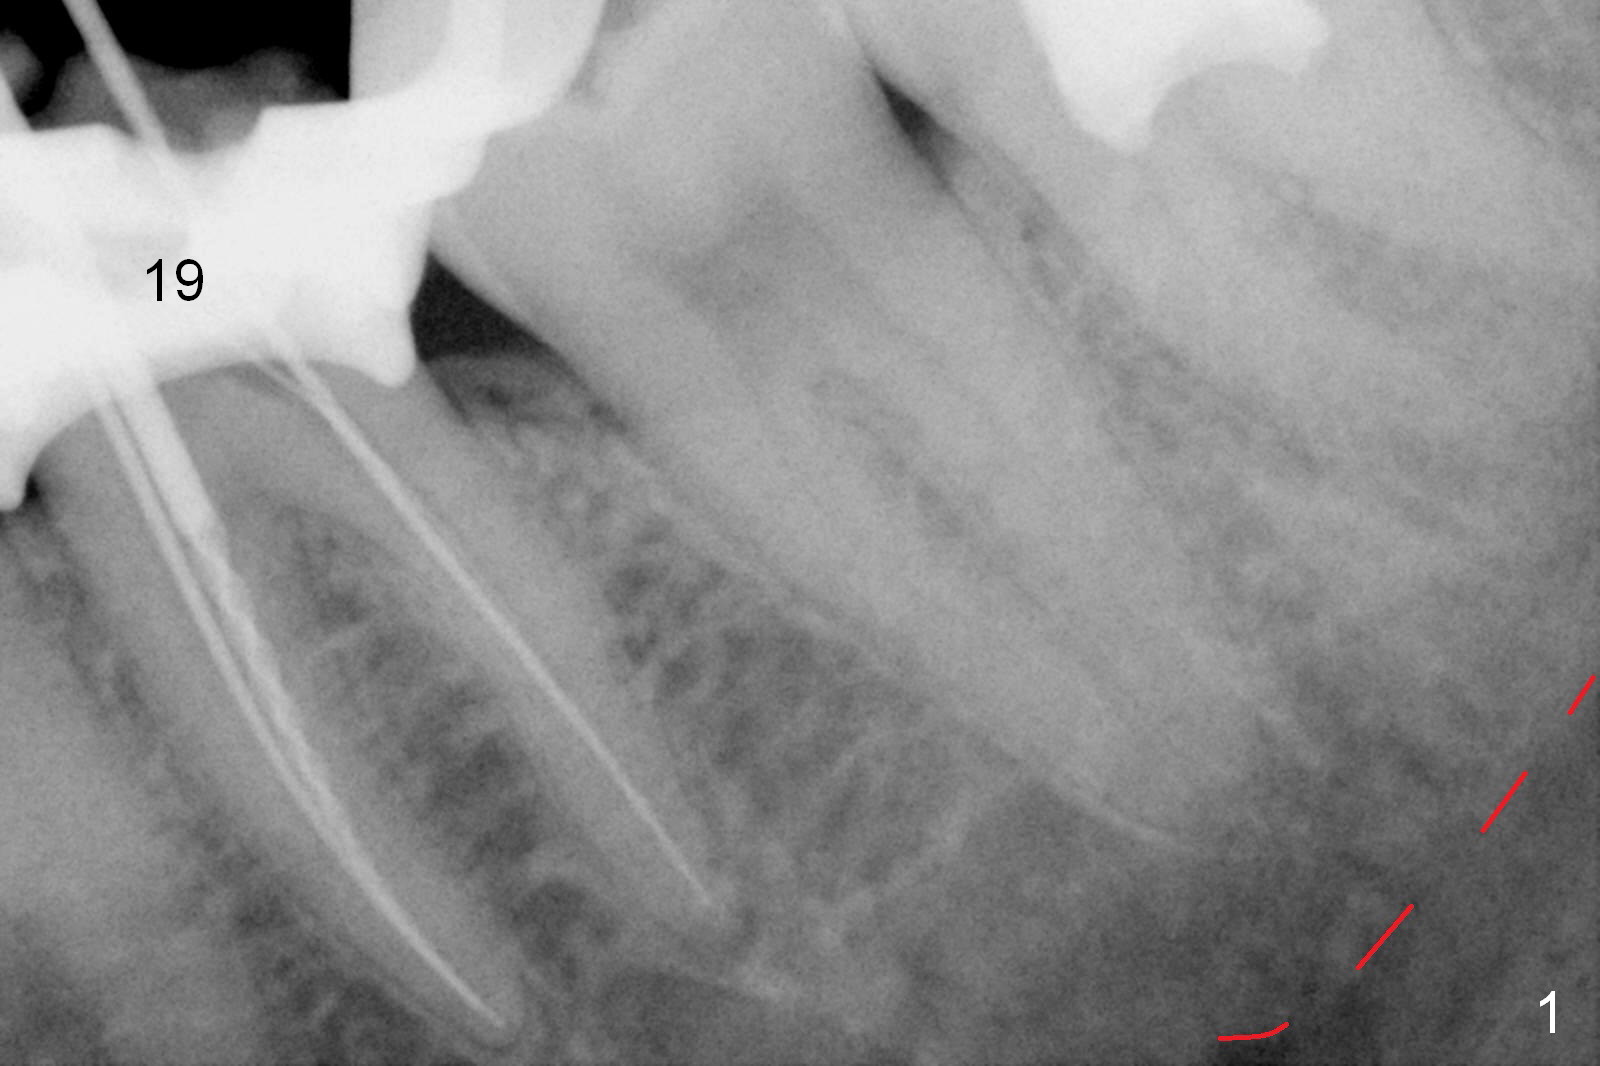

A 59-year-old woman had root canal therapy for the tooth #19 10.5 years ago (Fig.1 (red dashed line: the superior border of the Inferior Alveolar Canal). Two years later there was apparent periapical radiolucency with the distal root (Fig.2 *). The tooth remains asymptomatic until the last six months. There are 2 fistulae associated with the tooth: mesiolingual and buccal furca. Radiogra-phically, there are 2 radiolucent lesions: mesial and apical to the mesial root (Fig.3 *). If a 16 mm implant is placed, there will be approximately 5 mm apical bone (Fig.4); 7 mm for a 18 mm implant. The bone height is 25 mm (Fig.6). Therefore, once initial osteotomy is established with a 13 mm long drill with PA confirmation, the osteotomy is extended to its depth with 1.5x21 mm drill (Fig.5). After socket treatment with Metronidazole gauze with Epinephrine (1: 50,0000), take PVS impression of the socket to catch the large mesial defect. A fair amount of allograft and Osteogen is expected. It has been 9 months since last visit. Retake PA before surgery. If the mesial defect enlarges, start osteotomy in the distal slope of the septum.